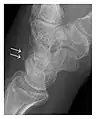

High-energy trauma fractures

Occult osseous injuries may result from a direct blow to the bone by compressive forces of adjacent bones against one another or by traction forces during an avulsion injury. Lesions in the tibial plateau, hip, ankle, and wrist are often missed. In a tibial plateau fracture, any disruption of the posterior and anterior cortical rims of the plateau should be sought. Impaction of subchondral bone will appear as an increased sclerosis of the subchondral bone (Figure 1). In the hip, posterior acetabular fractures also present subtle radiographic findings. The acetabular lines should then be carefully examined keeping in mind that the posterior rim, which is harder to see on X-rays, is more frequently fractured than the anterior rim (Figure 2). In the wrist, detection of carpal bone fractures is often challenging, with up to 18% of scaphoid fractures radiographically occult. Carpal fractures, especially the scaphoid, are associated with the risk of avascular necrosis. In apparently normal wrist radiographs from symptomatic patients, if there is history of a fall on an outstretched hand with pain in the anatomic snuffbox, suggesting scaphoid injury, the initial examination with posteroanterior, lateral, and pronation oblique views must be complemented by other specific views such as supination oblique and the "scaphoid" view A careful examination of cortices for evidence of discontinuity or offset and cancellous bone for lucency is necessary (Figure 3).[1]

Figure 1: A 56-year-old woman presenting with left knee pain after a fall. (a) Initial anteroposterior radiograph was considered normal, however, subtle cortical disruption of the anterior rim of the medial tibial plateau, medial to the tibial spine, is noted (arrow). (b) Coronal T1-weighted MRI confirms the cortical disruption (arrow) and shows extensive fracture through the proximal tibia. (c) Coronal proton density-weighted image with fat saturation shows extensive edema in the subchondral bone. Note also hypersignal adjacent to the medial collateral ligament corresponding to a grade I sprain (arrowheads).[1]